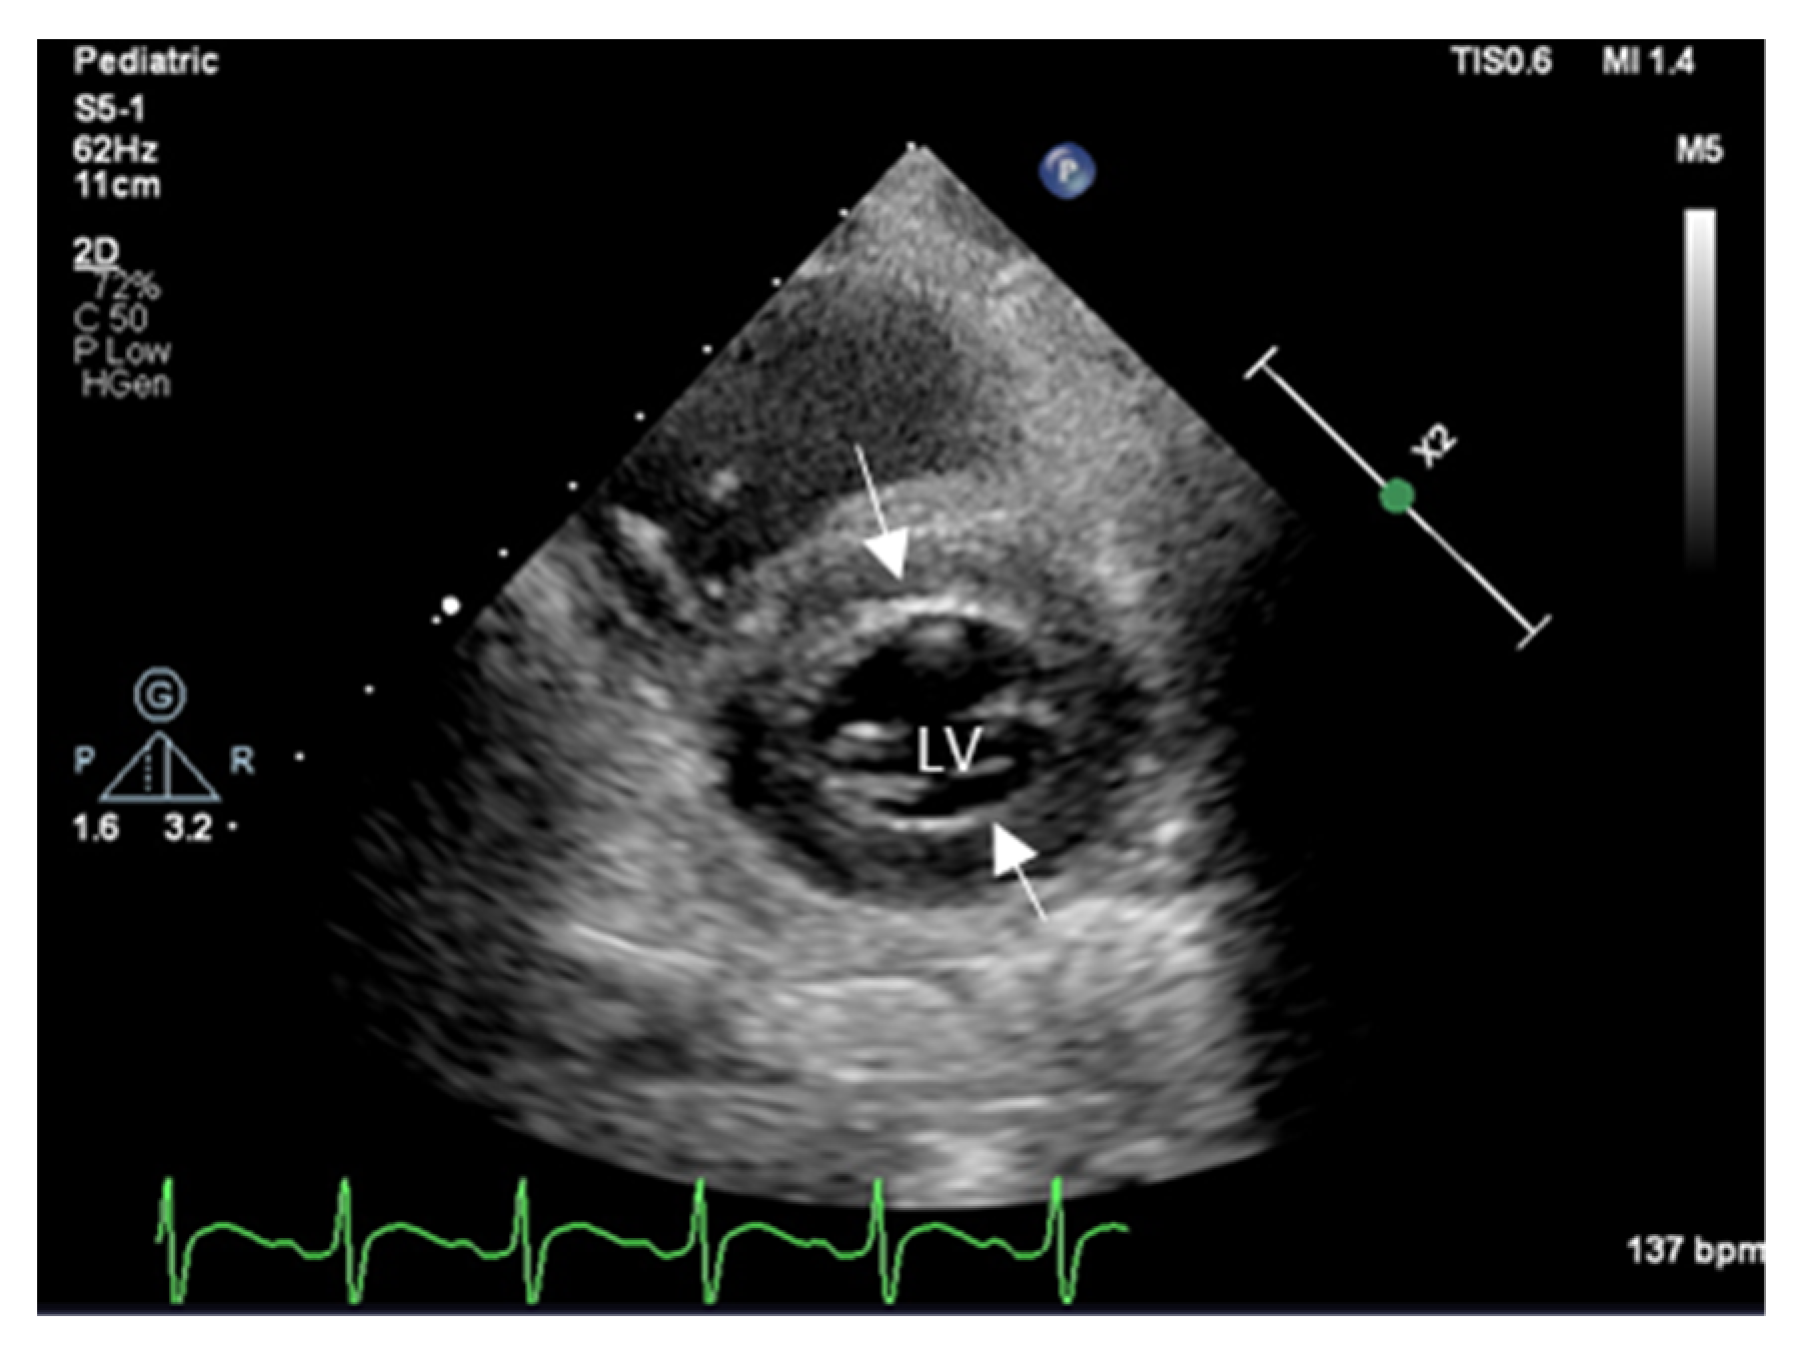

In the first few days after HT, there is usually an increase in the left ventricular (LV) thickness due to edema, increased perfusion, and inflammatory cell infiltration (Figure 1). Left ventricular mass and wall thicknesses generally normalize within three months, and LV diastolic dysfunction normalizes in 3 to 6 months after HT. Therefore, the presence of LV hypertrophy immediately after HT is considered a normal remodeling process. In addition, Z-scores for LV wall thickness and indexed LV mass are helpful in describing characteristic findings of LV hypertrophy when the heart is from an oversized donor.

Figure 1. Two-Dimensional echocardiography shows a short axis of LV with increased wall thickness due to edema and inflammation immediately after heart transplantation; arrows point to thickened interventricular sept, and LV posterior wall thickness increased (z score + 2).